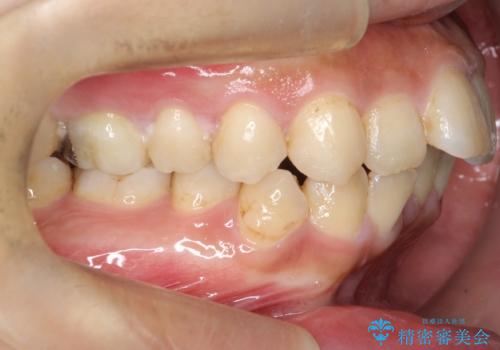

- 主訴:学生時代に矯正治療したが、後戻りしてしまった。上下前がのガタつきを治したい。

食品関係に努めており、頻繁に物を口にするためマウスピース矯正は装着時間を守ることが難しいことから非抜歯のワイヤー装置にて治療することとなりました。

ワイヤー矯正(審美装置)非抜歯 治療期間:1年8か月

一日に物を口にする回数が多い方はマウスピース矯正における推奨装着時間を守ることや、その都度歯磨きをすることが難しいため、ワイヤー矯正での治療となりました。

途中、大臼歯の遠心移動のためリンガルアーチを使用しています。